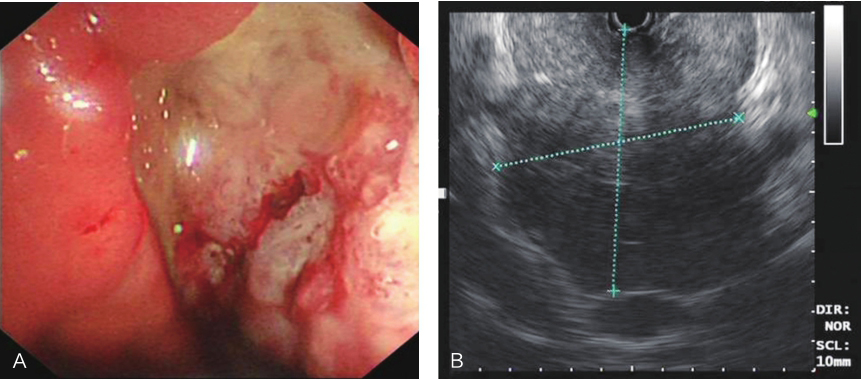

电子超声胃镜:内镜下见胃体小弯侧巨大溃疡,底覆污秽苔,超声扫描显示胃体小弯侧巨大低回声占位病灶,病灶大部分凸向腔外,切面大小约8cm×8cm,与肝脏界限清晰,腹腔内未见明显肿大淋巴结(图1)。

图1超声胃镜提示胃体小弯侧巨大低回声病灶,切面约8cm×8cm

A.胃镜;B.超声内镜